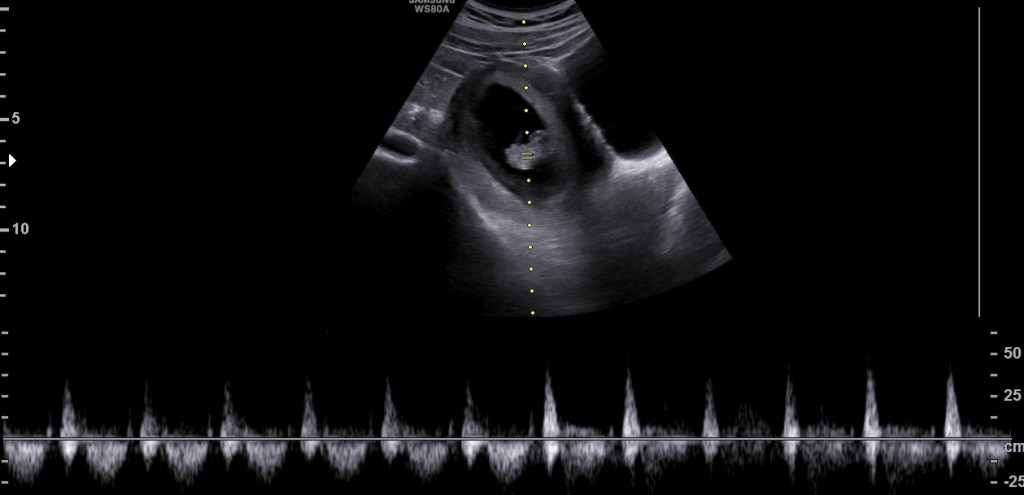

- La Noticia

Ya habían pasado dos semanas y en la primera prueba… Lee más: La Noticia